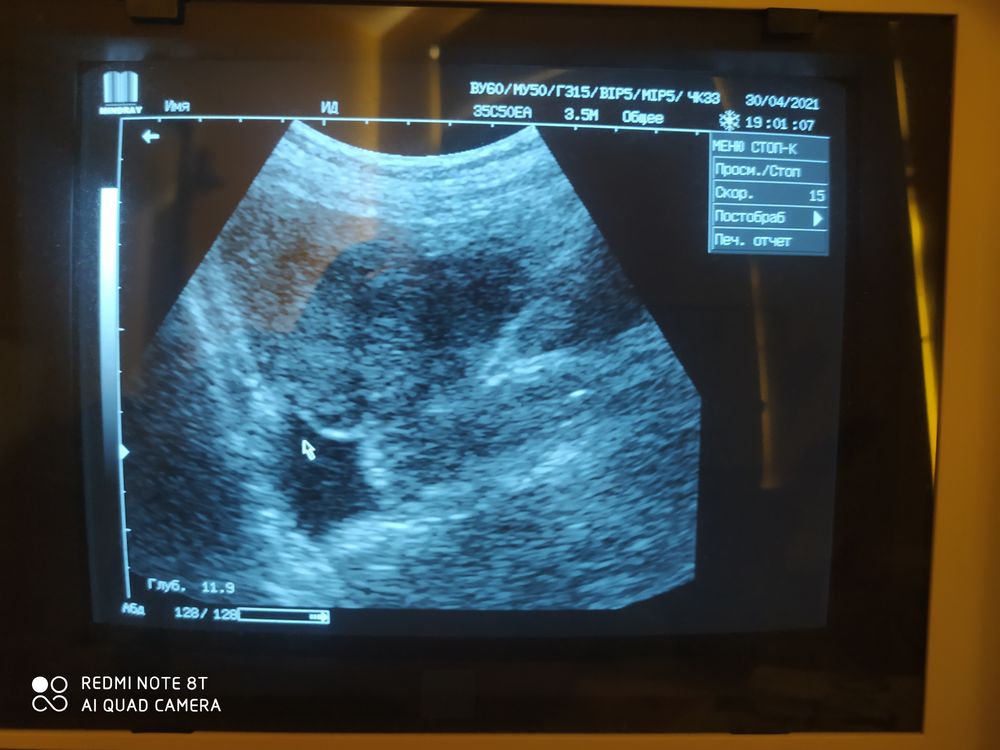

Первое фото где киста, второе фото-жидкость за маткой! Кто нибудь разбирается в этих снимках?)

Здравствуйте, задержка 5 дней, тест положительный! вчера ходила на УЗИ, врач беременность не подтвердил, но сказал в матке киста, и за маткой небольшая жидкость! Эндометрий 14,6